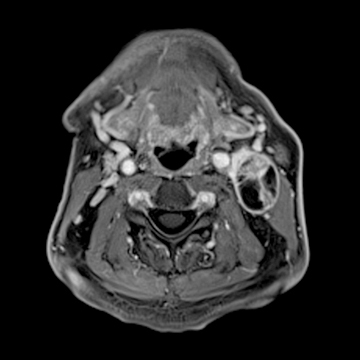

頚部腫瘍

- 造影3D VIBE

- 体動の影響を受けにくい